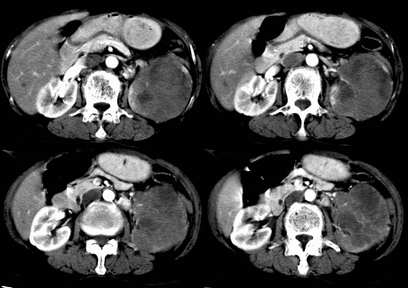

病患,女,69岁,左侧腰部不适,偶感疼痛2个月余,无化验室检查,行彩超发现左侧肾区实质性肿物,后行ct检查,结果同上。

左肾不规则软组织肿块,内见低密度坏死区,与正常肾实质分界不清,左肾明显增大,增强呈不规则条索状强化,肾盂及左输尿管上段扩张。肾周脂肪层受侵、模糊。印象:典型左肾癌。

平扫,表现为肾实质肿块,呈分叶状,肿块密度不均,内有不规则低密度区(陈旧性出血?坏死?)有的似呈囊性,增强明显不均一强化,与肾实质相比呈相对低密度的不均一肿块,肾周脂肪间隙可见,肾前筋膜未见增后,肾血管及腹主动脉旁未见肿大淋巴结影

左侧肾癌并肾静脉癌栓.腹膜后淋巴结肿大转移.

左肾癌累及左输尿管,左肾静脉无受累征象。